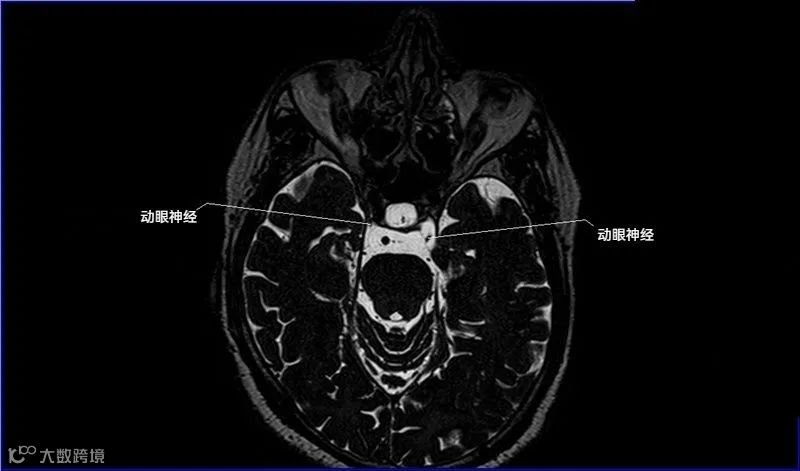

一嗅二视三动眼,四滑五叉六外展,

七面八听九舌咽,迷走及副舌下全。